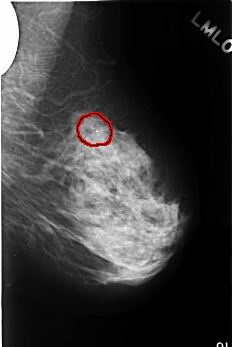

FILE: C_0379_1.LEFT_MLO.OVERLAY TOTAL_ABNORMALITIES 1 ABNORMALITY 1 LESION_TYPE CALCIFICATION TYPE PLEOMORPHIC DISTRIBUTION CLUSTERED ASSESSMENT 4 SUBTLETY 5 PATHOLOGY BENIGN TOTAL_OUTLINES 1 BOUNDARY |